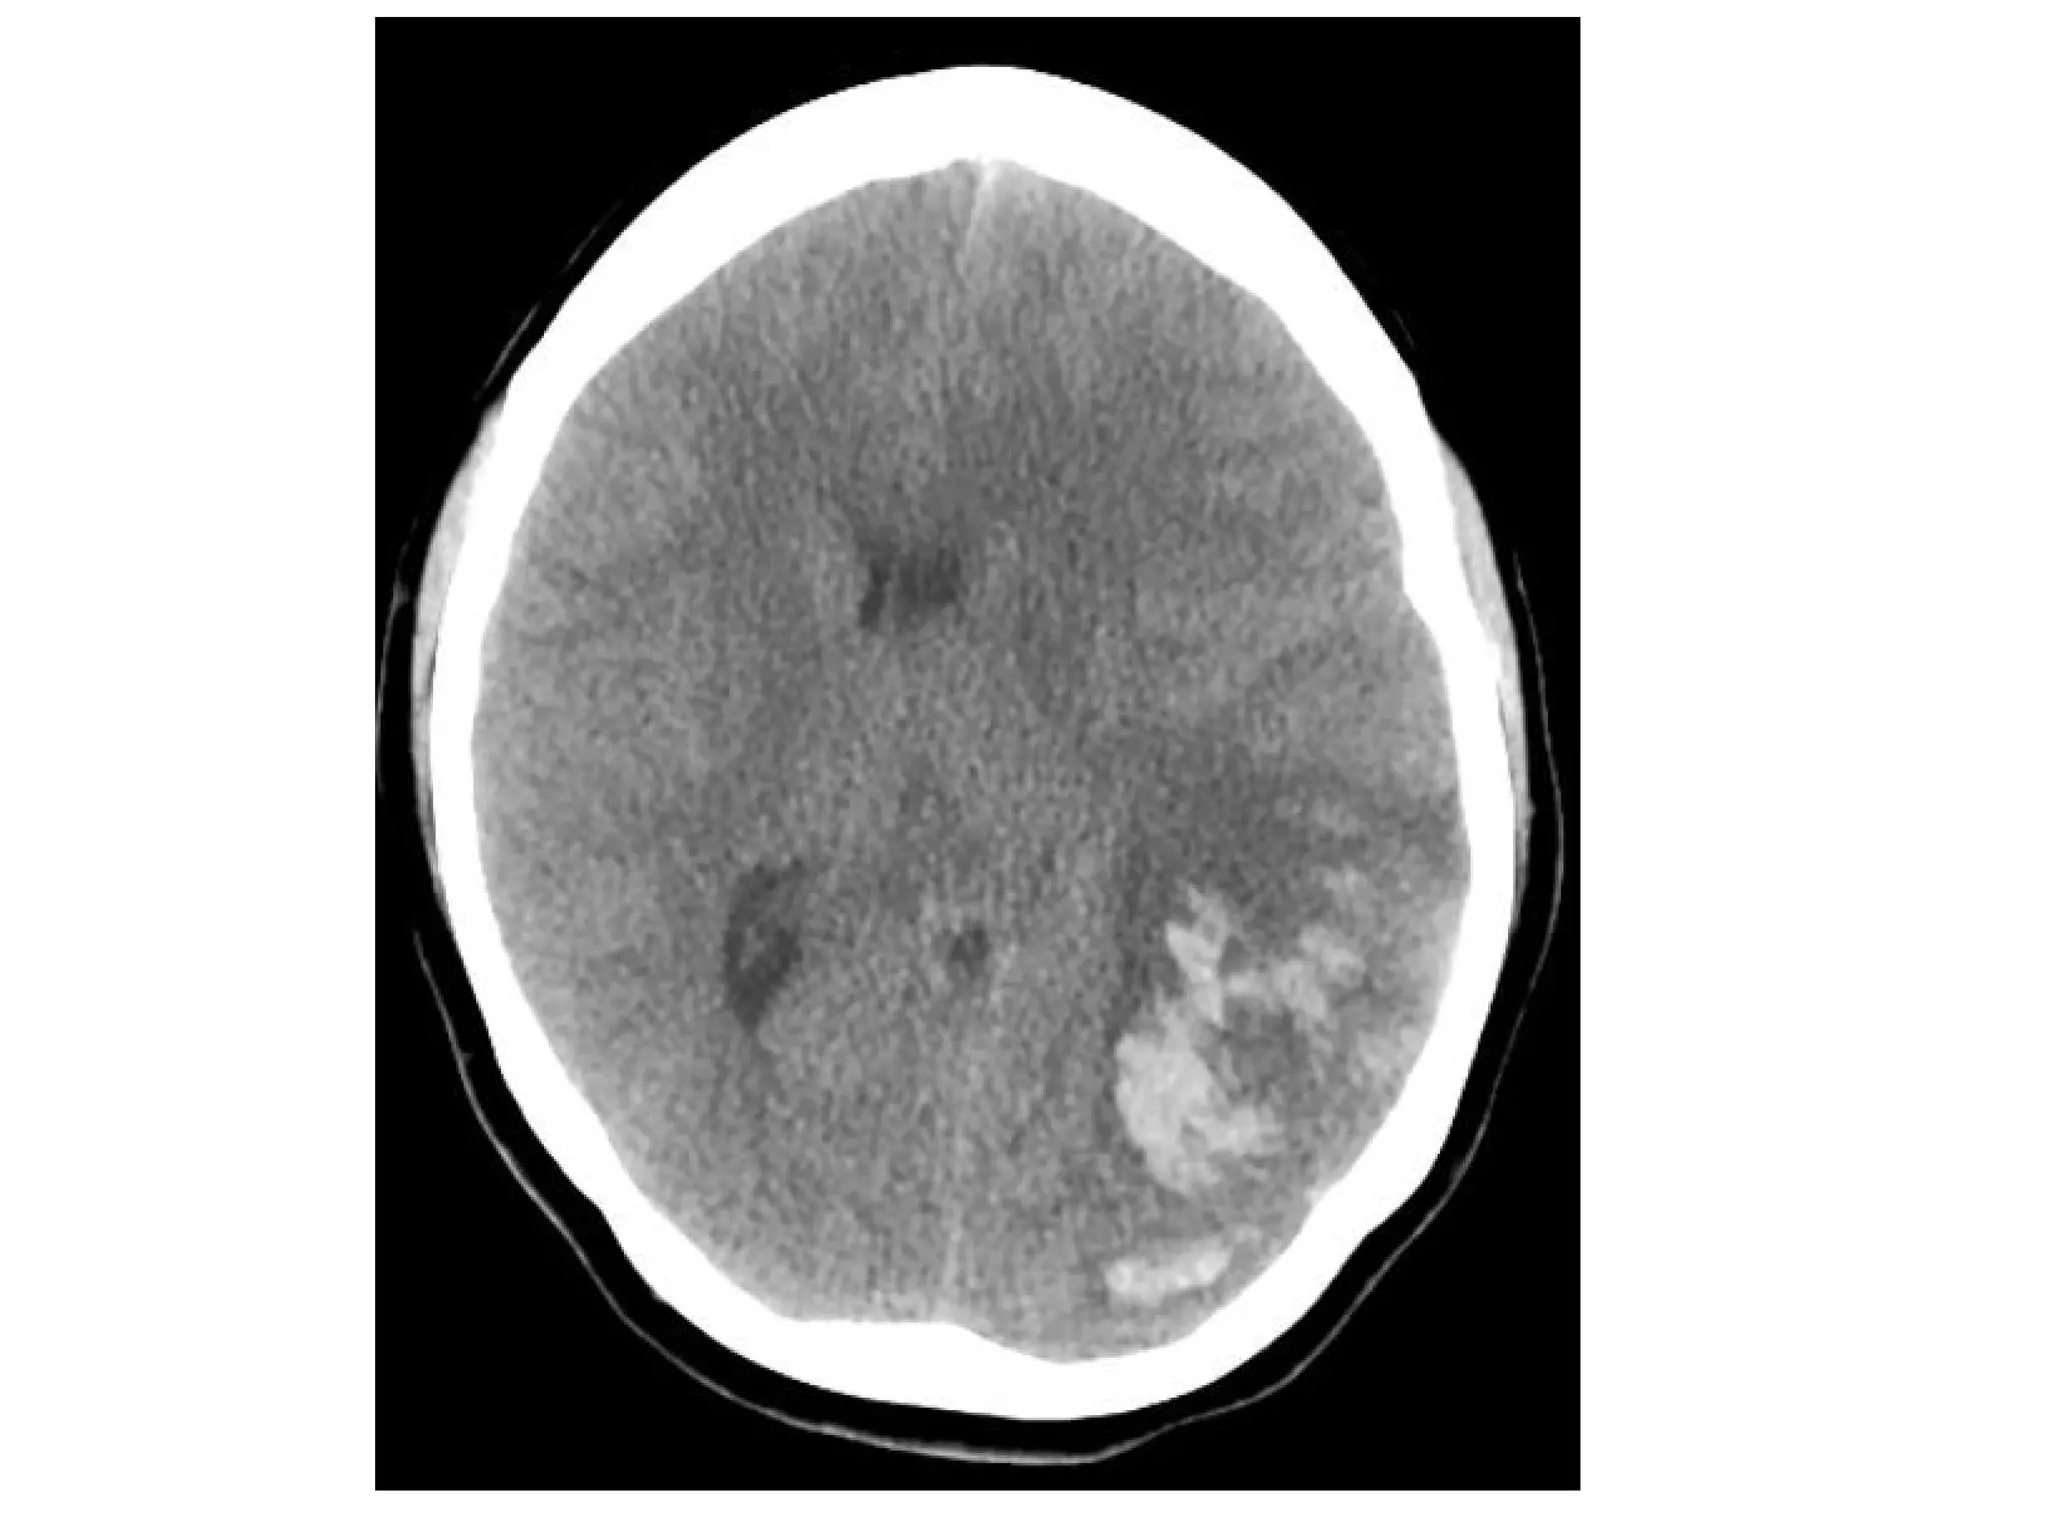

Hemorrhagic infarction in the temporal lobe (red arrow) , notice the dense

transverse sinus due to thrombosis (blue arrows)